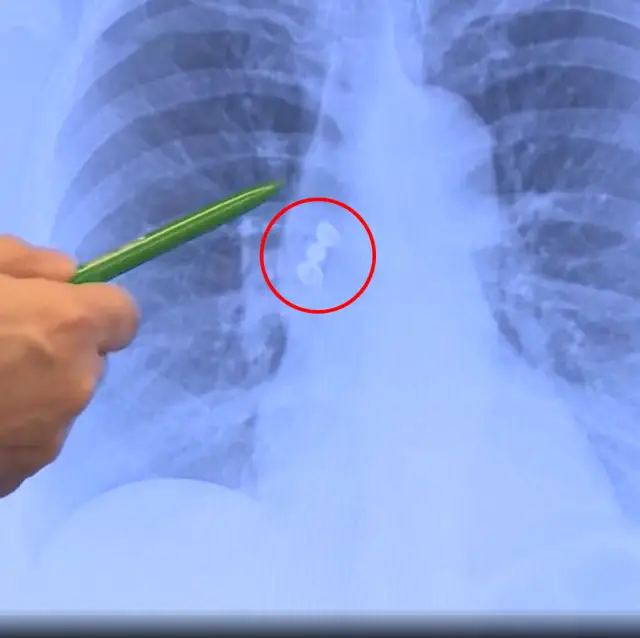

Röntgen sonuçları, diş kaplamalarının bronş yoluyla akciğere kaçtığını gösterdi. Bu nadir durum, bronkoskopi adı verilen bir endoskopik prosedürle tespit edildi ve kaplamalar akciğerden çıkarıldı.

Hasta, göğüs röntgeni ve bilgisayarlı tomografi (BT) taramaları sayesinde kaplamaların solunum yollarına yerleştiği belirlendi. Uzman göğüs hastalıkları doktorları, bronkoskopi yöntemiyle akciğer içinde kaplamaları yakalayıp çıkardı.